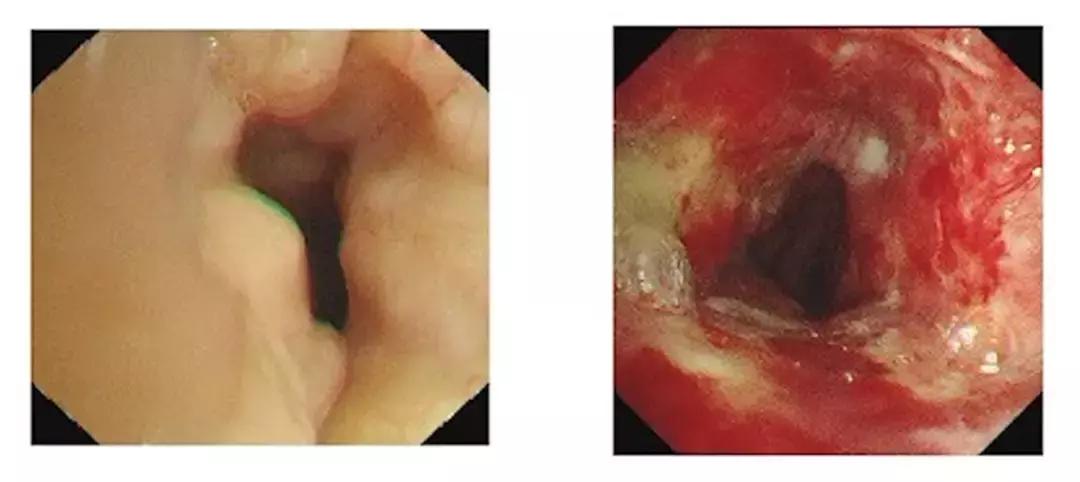

气管镜示:声门狭窄,声带表面多发结节样增生,活动差。声门下长约 5.5 cm气管管腔狭窄、多发结节样增生、表面充血、水肿明显。远端气管通畅。患者误诊多年,最终于我院行气管镜取病理确诊为气管淀粉样变。

王洪武副院长凭借丰富气管镜治疗经验,采取硬镜铲切、高频针型电刀旋切的策略,综合应用冷冻、氩气刀、钳取等多种方法,高效率的切除患者增厚的气道粘膜,解除管腔狭窄。术后患者呼吸困难明显缓解出院。2 周后来院再次复诊气管镜管腔狭窄较前明显改善。

左:患者术前管腔狭窄 右:两周后复查气管镜